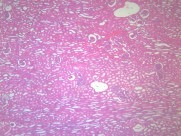

肾小管renal tubule 与肾小囊壁层相连的一条细长上皮性小管,具有重吸收(reabsorption)和排泌作用(secretion).肾小管按不同的形态结构,分布位置和功能分成三部分;近端小管,细段和远端小管。肾小管在肾髓质中。